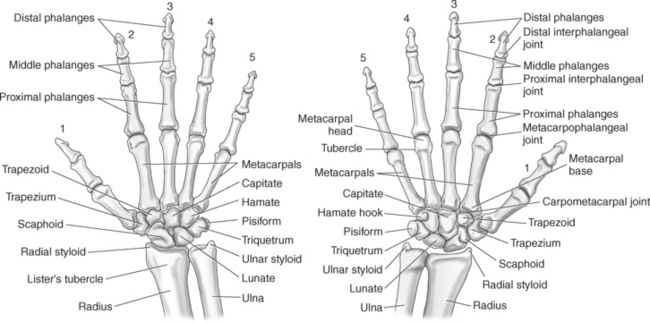

The bony anatomy of the wrist and hand consists of the distal radius and ulna, 8 carpal bones, 5 metacarpals, and 14 phalanges (Figure 9.101). Both the distal radius and ulna have a conical styloid process that acts as an attachment site for ligaments. The radial styloid process is located on the lateral surface of the radius, whereas the ulnar styloid process is located on the posteromedial side of the ulna. The carpal bones are arranged in proximal and distal rows. Located in the proximal row of carpal bones are the scaphoid (navicular), lunate (semilunar), triquetral (triquetrum), and pisiform bones. The pisiform is considered a sesamoid bone that is embedded in the tendon of the flexor carpi ulnaris. The distal row consists of the trapezium (greater multangular), trapezoid (lesser multangular), capitate (os magnum), and hamate (unciform) bones (Figures 9.102 through 9.114). The five metacarpals are small tubular bones with a proximal end (base), distal end (head), and shaft (body). The 14 phalanges that make up the fingers are short tubular bones. Like the metacarpals, each phalanx consists of a proximal (base), middle (body or diaphysis), and distal (head) portion. Each digit consists of 3 phalanges (proximal, middle, and distal), except for the thumb (first digit), which has only 2 phalanges (proximal and distal). The articulation of the phalanges of the second through fifth digits creates three interphalangeal joints: the metacarpophalangeal (MCP) joints classified as condyloid joints, proximal interphalangeal (PIP), and distal interphalangeal (DIP). The proximal and distal interphalangeal joints are classified as hinge joints (Figure 9.101). The first digit, which consists of 2 phalanges, has just two joints: the MCP joint, classified as a saddle joint, and an interphalangeal joint, classified as a hinge joint (Figure 9.101).

The joints of the wrist and hand are quite complex and consist of the following: distal radioulnar articulation, radiocarpal articulation (proximal joint of hand), midcarpal articulation (distal joint of hand), intercarpal articulations (articulations between proximal and distal carpals), carpometacarpal articulations (between carpals and metacarpals), the intermetacarpal articulations (between bases of metacarpals two through five) and the interphalangeal joints (between phalanges of each digit) (Figures 9.111 and 9.115). The distal radioulnar articulation, also called the distal radioulnar joint (DRUJ), is created when the ulnar notch of the radius moves around the articular circumference of the ulna, providing the movements of supination and pronation. The main stabilizing element of the DRUJ is an articular disk called the triangular fibrocartilage complex (TFCC). The TFCC is a fan-shaped band of fibrous tissue that originates on the medial surface of the distal radius and traverses horizontally to insert on the ulnar styloid process (Figures 9.115 and 9.116). It rotates against the distal surface of the ulnar head during pronation and supination and separates the ulna from the carpal bones. The proximal surface of the radiocarpal articulation is formed by the articular carpal surface of the radius and the TFCC, whereas the distal surface is formed by the articular surfaces of the scaphoid, lunate, and triquetrum and the interosseous ligaments connecting them (Figures 9.111 through 9.115). The midcarpal joint is formed by the articulations between the proximal and distal carpal rows (Figures 9.110 and 9.115). The articulation between the carpals within each row creates the intercarpal joints (Figures 9.111 and 9.115). The carpometacarpal joints are formed by the articulations between the carpus and the five metacarpals (Figure 9.111 and 9.115). The carpometacarpal joint of the thumb is an independent joint formed by the articular surfaces of the trapezium and first metacarpal, creating a pure saddle joint. The carpometacarpal articulations of the two to five digits are amphiarthrotic joints with little mobility (Figures 9.105 and 9.115). The intermetacarpal articulation exists between the base of the metacarpals and is joined by the palmar and dorsal metacarpal ligaments (Figure 9.115).